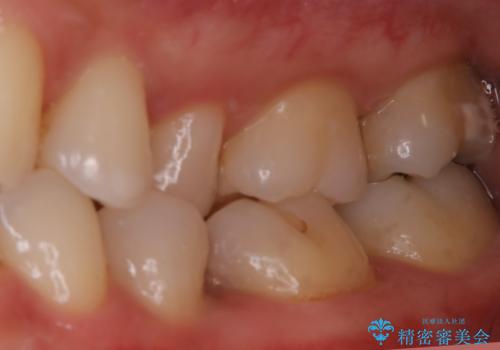

適合不良の補綴物は二次的な虫歯発生のリスクが高まります。

自費診療で用いられる材料は保険適応の材料に比べて、より精密で適合の良い被せ物作ることができるため、長期的な虫歯のリスクを大幅に減らすことが可能です。

今後は他の銀歯のやり替えも順次行っていくこととなりました。